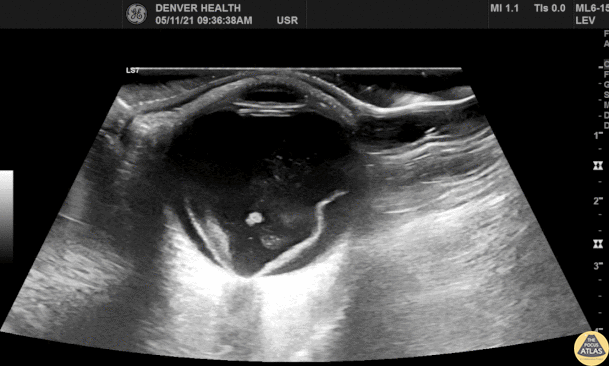

Orbital - Retinal Detachment

52M PMH L cataract surgery presented with painless left eye vision loss preceded by flash. POCUS performed in the ED demonstrated a left sided retinal detachment with macula attached (“mac-on”), with retinal hemorrhage as well. Ophthalmology was consulted, and the patient was taken urgently to the OR for vitrectomy and retinal repair. Dr. Michael Kidon, PGY3 Denver Health Residency in Emergency Medicine